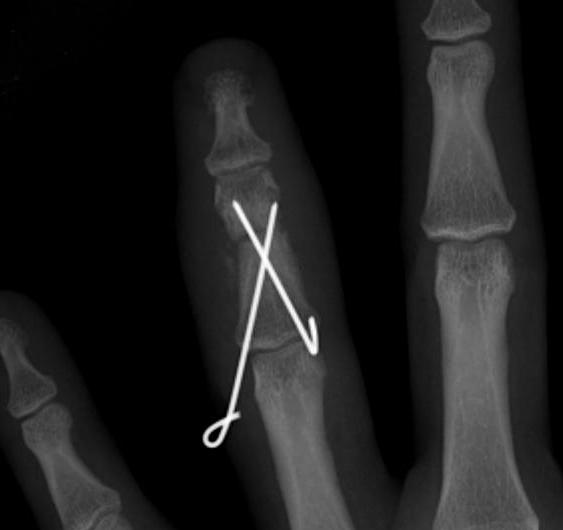

A. Transverse fractures

- cross K wire

- Lister’s intra-osseous wire fixation

- plating